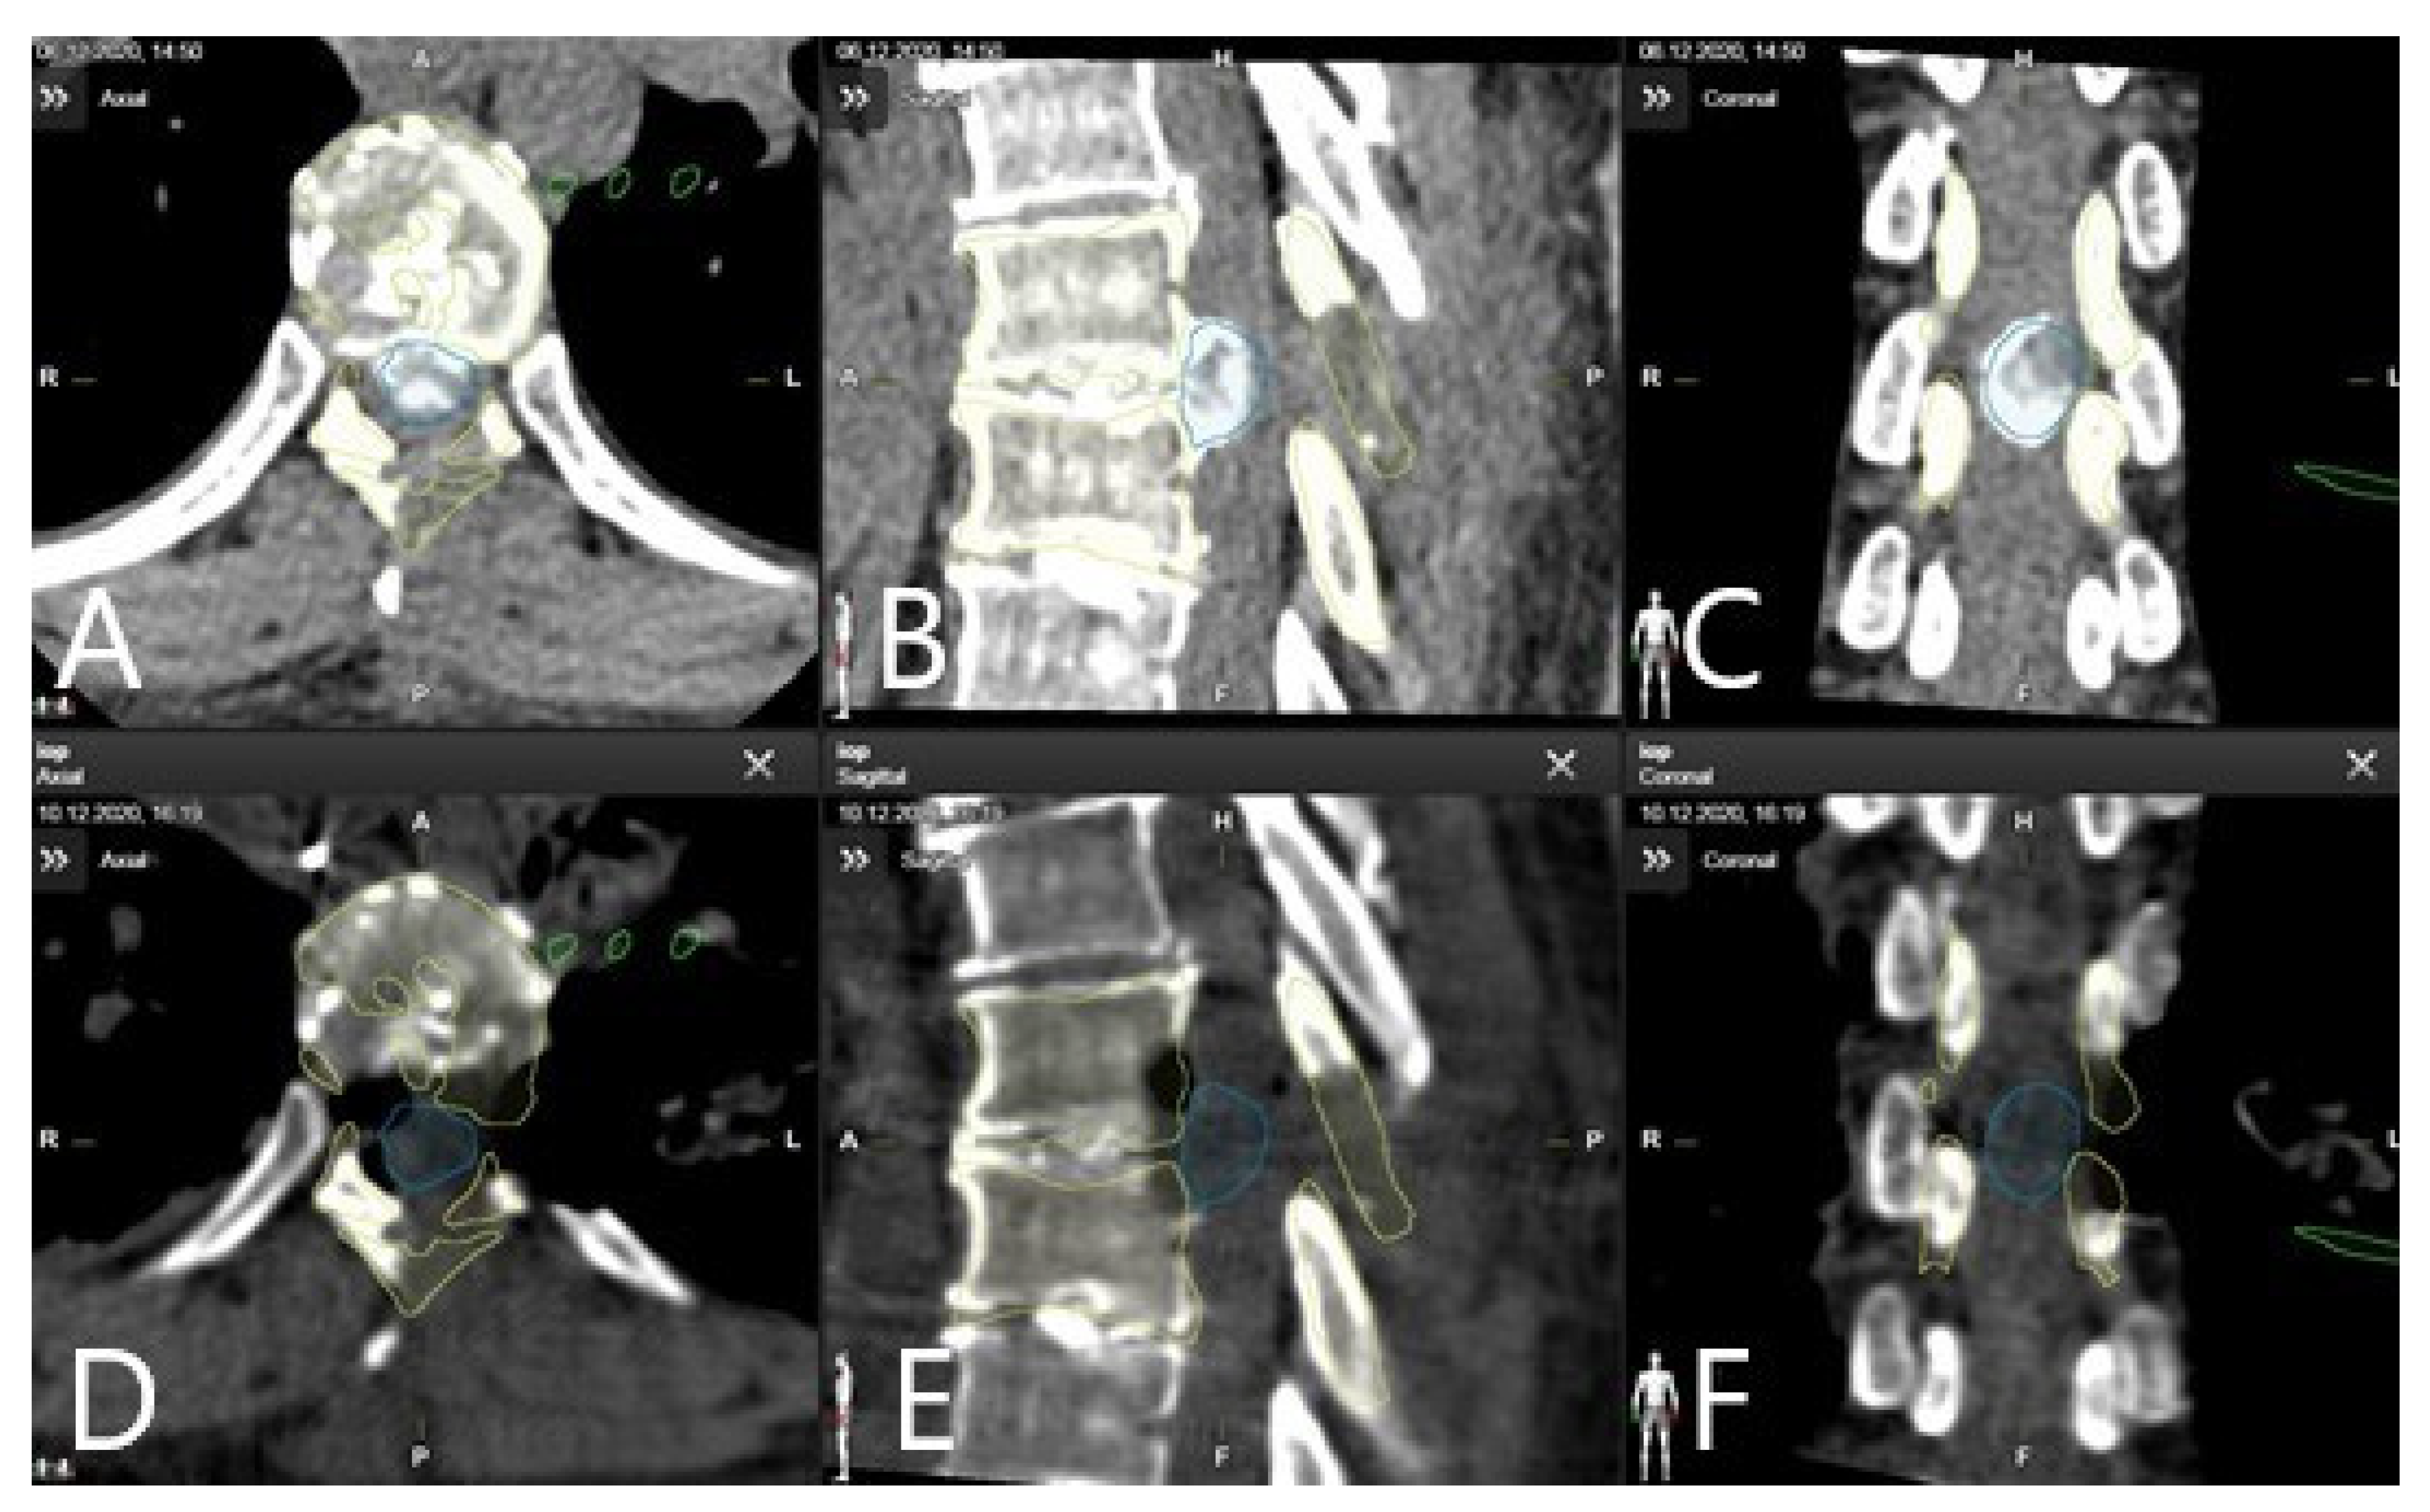

3.4. Augmented Reality

3.5. Clinical Application of iCT and AR